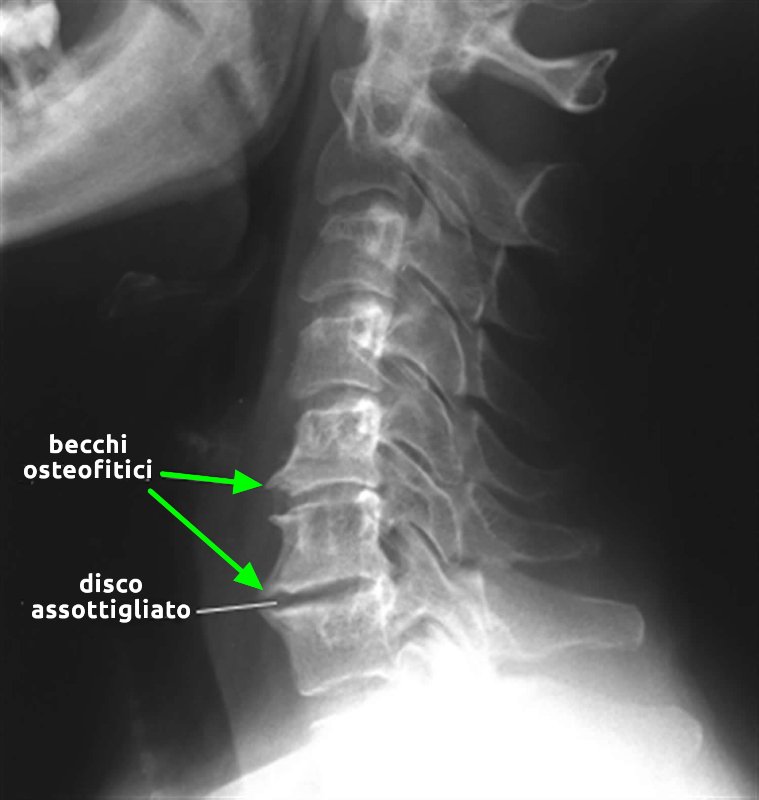

Osteofiti

- Descrizione: Escrescenza di tessuto osseo localizzata in prossimità della superficie articolare di un osso.